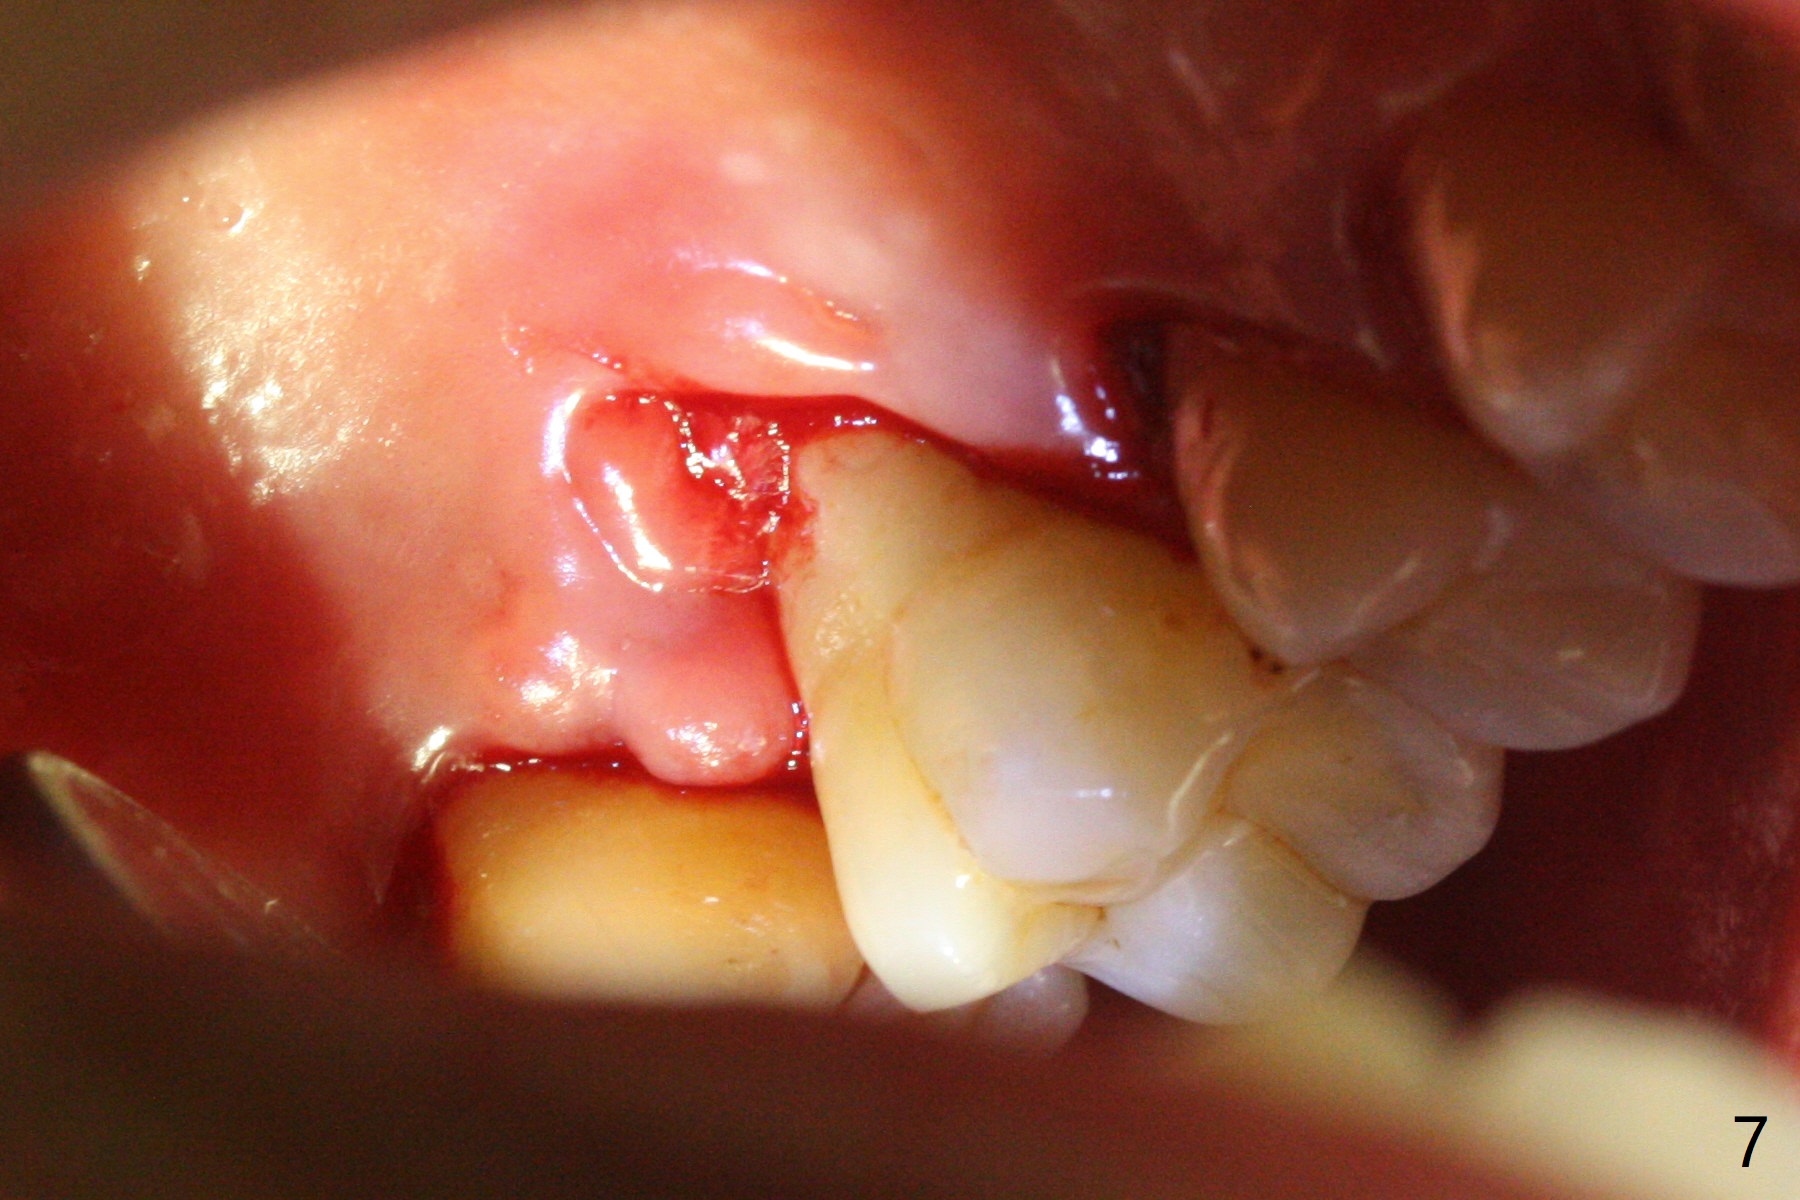

A 45-year-old man has chronic generalized moderate localized severe periodontitis; gingival recession is severe lingual of the tooth #14 with mobility II (Fig.1). The low bone density outline (Fig.1 white dashed line) is larger than the roots, suggesting lingual bone loss/low lingual crest. Although the bone height seems to be 11 mm (Fig.2), the bone responsible for primary stability of an implant will be apical (Fig.3 *,4). The implant platform will be ~3 mm subcrestal buccal, while ~3 mm supragingival lingual (Fig.5). The diameter of the implant will not be too large, 4.5 mm (dummy). There will be not biologic width issue. The large perimplant gap will be closed with sticky bone. Severe palatal gingival recession is shown pre- (Fig.6) and post- (Fig.7) SRP. #30 Gutta Percha inserted palatal reaches the highest point of the low bone density lesion (Fig.8). Pulpal test and CT will determine that endodontic treatment can regrow bone or that socket preservation is needed with Cytoplast.